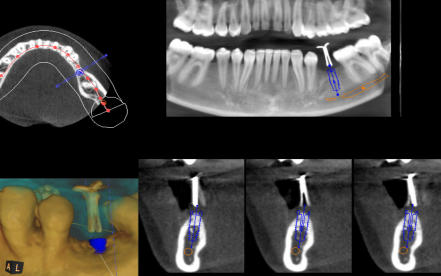

Die 3D-Röntgentechnik oder digitale Volumentomographie liefert 3-dimensionale Ansichten der Kiefer und der Zähne und ist ein großer Gewinn für die zahnärztliche Diagnostik. Bestimmte krankhafte Prozesse werden nur mit diesem Verfahren dargestellt. Häufig werden auch bisher versteckte Befunde entdeckt. Implantatplanungen können mit 3D-Röntgenaufnahmen präziser und vor allem sicherer vorgenommen werden. Exakte Vermessungen sind in diesen Ansichten möglich. Wurzelbehandlung (Endodontie) lassen sich sicher durchführen. Die 3D-Technik ermöglicht ein exaktes Erkennen der Wurzelanatomie, Lokalisieren und Vermessen der Wurzelkanäle. Parodontalbehandlungen (regenerative Parodontologie) lassen sich im Voraus planen. Dadurch kann die Behandlung gezielt und schonend durchgeführt werden. Weitere diagnostische Anwendungsgebiete der digitalen Volumentomographie liegen im Bereich der zahnärztlichen Chirurgie, z.B. für schwierige Weisheitszahnentfernungen, Lagebestimmungen von verlagerten Zähnen und Fremdkörpern.

Mit unserem modernen DVT erstellen wir 3D-Röntgenaufnahmen im Vergleich zu anderen Geräten besonders strahlungsarm. DVT´s sind insbesondere im Vergleich zu Computertomographien “CT´s” vielfach strahlungsärmer.

Wir haben uns durch spezielle Weiterbildungen zur Auswertungen von Volumentomographien (DVT) für 3D-Planungen zertifiziert.